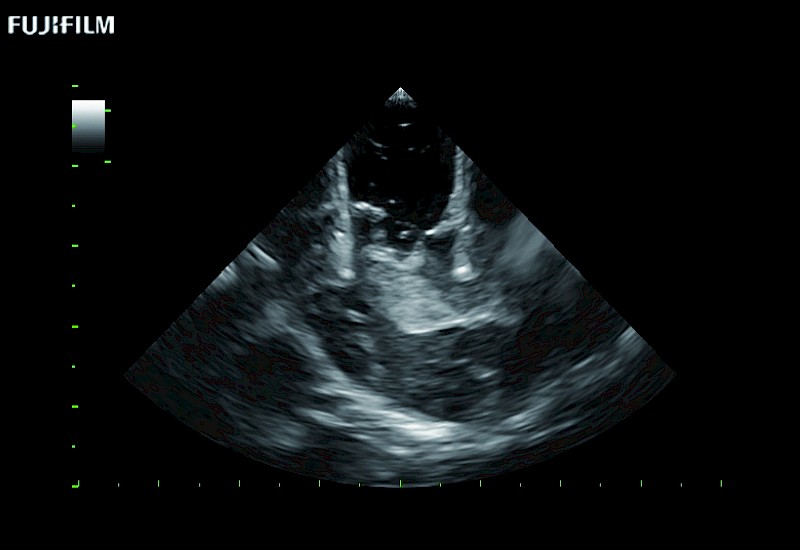

The world's only phased array burr-hole transducer that is ideal for scanning during burr-hole guidance procedures.

Main Specifications: